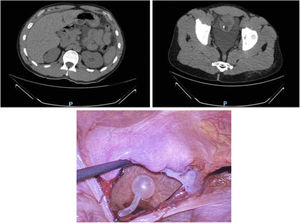

A 30-year-old male with no history of trauma came to the Emergency Department due to anuria and belt-like epigastric pain over the previous 24-h after having abused drugs and alcohol. The examination showed: sweating, HR 94 bpm, and abdomen with no signs of peritonism or visible external injuries. Lab work showed: leukocytosis 17,000, creatinine 3, GFR 20 and CRP 2. Abdominal CT scan revealed free fluid and supramesocolic pneumoperitoneum. Suspecting gastric perforation, we performed urgent exploratory laparoscopy and observed abundant serosanguineous free fluid. After exploring the supramesocolic quadrants, with no pathological findings, we identified a 5 cm perforation in the bladder dome (Fig. 1), which was repaired by continuous suture in 2 planes using 3/0 V-Loc™.